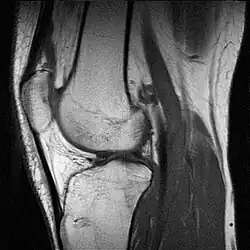

MRI van een knie

Met een MRI kan een hernia zo goed zichtbaar gemaakt worden, dat gebleken is dat heel veel mensen er klachtenvrij mee rondlopen. Het is dan ook zaak niet te snel over te gaan tot onderzoek en behandeling. Met MRI zijn de weke delen (alles behalve bot) van gewrichten goed af te beelden, zoals